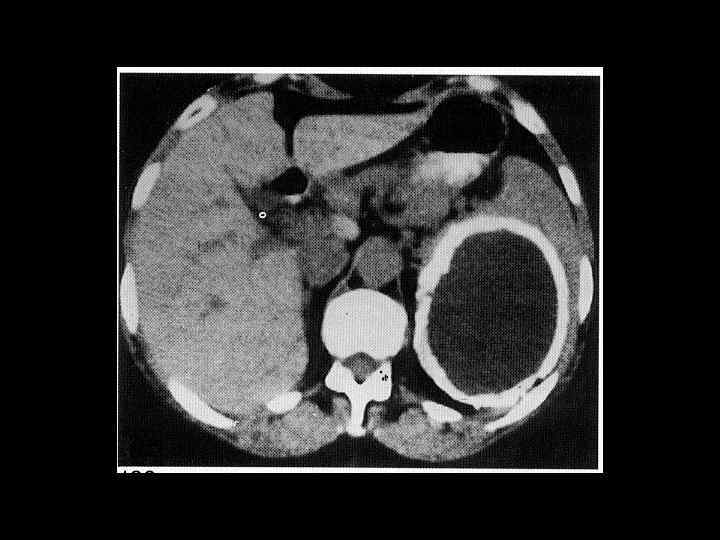

АКТУАЛЬНЫЕ ВОПРОСЫ РЕНТГЕНОЛОГИИ ЛУЧЕВАЯ ДИАГНОСТИКА ЗАБОЛЕВАНИЙ СЕЛЕЗЕНКИ Кисты и абсцессы селезенки

АКТУАЛЬНЫЕ ВОПРОСЫ РЕНТГЕНОЛОГИИ ЛУЧЕВАЯ ДИАГНОСТИКА ЗАБОЛЕВАНИЙ СЕЛЕЗЕНКИ Травма и инфаркт селезенки

АКТУАЛЬНЫЕ ВОПРОСЫ РЕНТГЕНОЛОГИИ ЛУЧЕВАЯ ДИАГНОСТИКА ЗАБОЛЕВАНИЙ СЕЛЕЗЕНКИ Опухолевое поражение селезенки